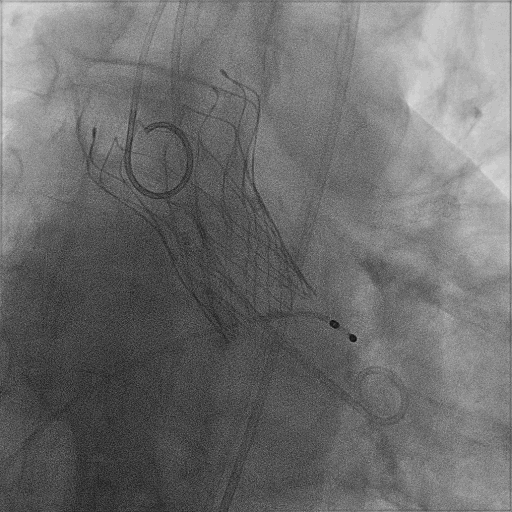

麻醉方式为全麻,建立静脉通路后,穿刺右侧股静脉,预埋ProGlide缝合器,食道超声指导下房间隔穿刺成功,鞘管扩张穿刺部位,沿导丝将导引导管送入左房,MitraClip调整后顺利到达二尖瓣目标位置,在X线及食道超声辅助下,将MitraClip NTR二尖瓣夹精确定位后,成功夹合二尖瓣A2-P2区,超声显示反流明显减少,多切面证实夹合组织充分,肺静脉多普勒波形由反向恢复正常,手术顺利结束,安返普通病房。

术中超声引导:

确定房间隔穿刺点:靠后

穿刺点高度测量:4.14cm

2D视图下测量大鞘长度2.2cm

2D视图下建立trajectory

3D视图打开夹子

3D视图下调Rotate,定位2区

X-plane:下夹子尝试捕获2区

夹子逐渐夹闭后,2区返流逐渐减少

3D:测量前叶长21.2mm,后叶长10.2mm

X-plane:计算前叶捕获长度6.8mm,后叶捕获长度6.5mm

夹子放置后二尖瓣口平均跨瓣压差:3mmHg

肺静脉血流频谱恢复正常

3D视图下观察二尖瓣双孔形态

3D-color:残余少量返流